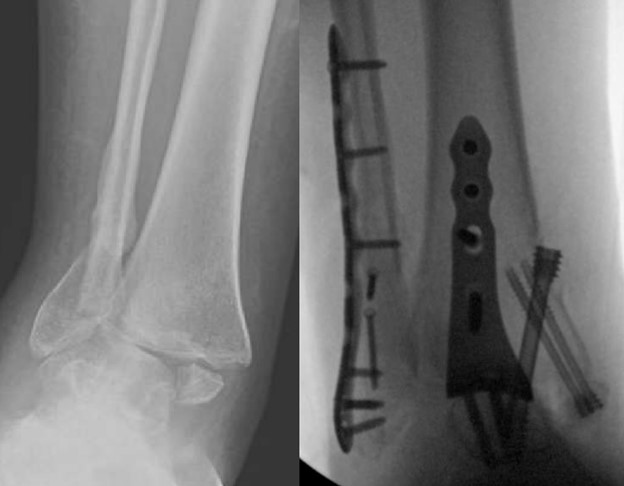

education. While he practices all aspects of foot and ankle surgery, he has made especially significant contributions in advancing our understanding of charcot arthropathy and Lisfranc injuries.